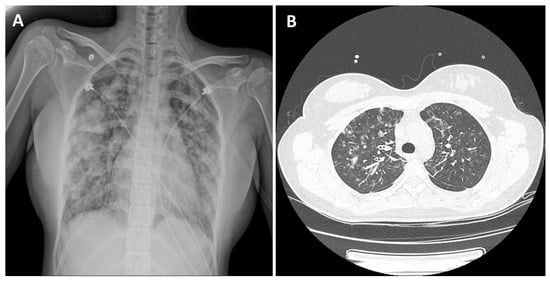

2. Case Presentation